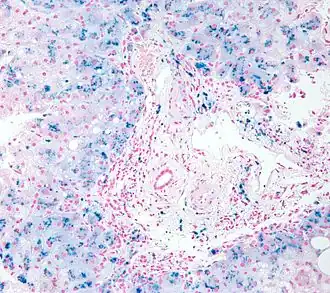

![]() Биопсия: гистологическая картина гемосидероза. | |

Окончательный диагноз может быть установлен при биопсии печени или МРТ печени и сердца в Т2-взвешенном режиме[14].